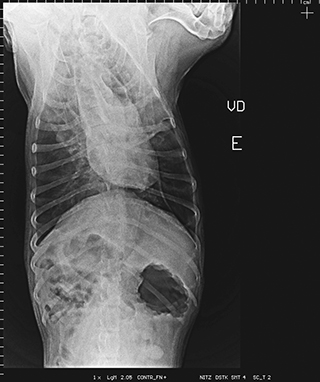

Radiologia Digital Direta / Digital Radiography

As radiografias geradas digitalmente podem ser transmitidas para iPad Apple®, notebooks e smartphones.

iPad com tela Retina Apple® possibilita a visualização das imagens com maior qualidade diagnóstica.

Envio Digital Automático (EDA) permite a distribuição das radiografias sem necessidade de impressão.

O responsável pelo paciente pode receber as radiografias em seu smartphone ou computador.

Radiologistas podem receber as imagens por e-mail para laudo, de forma prática. 100% DIGITAL